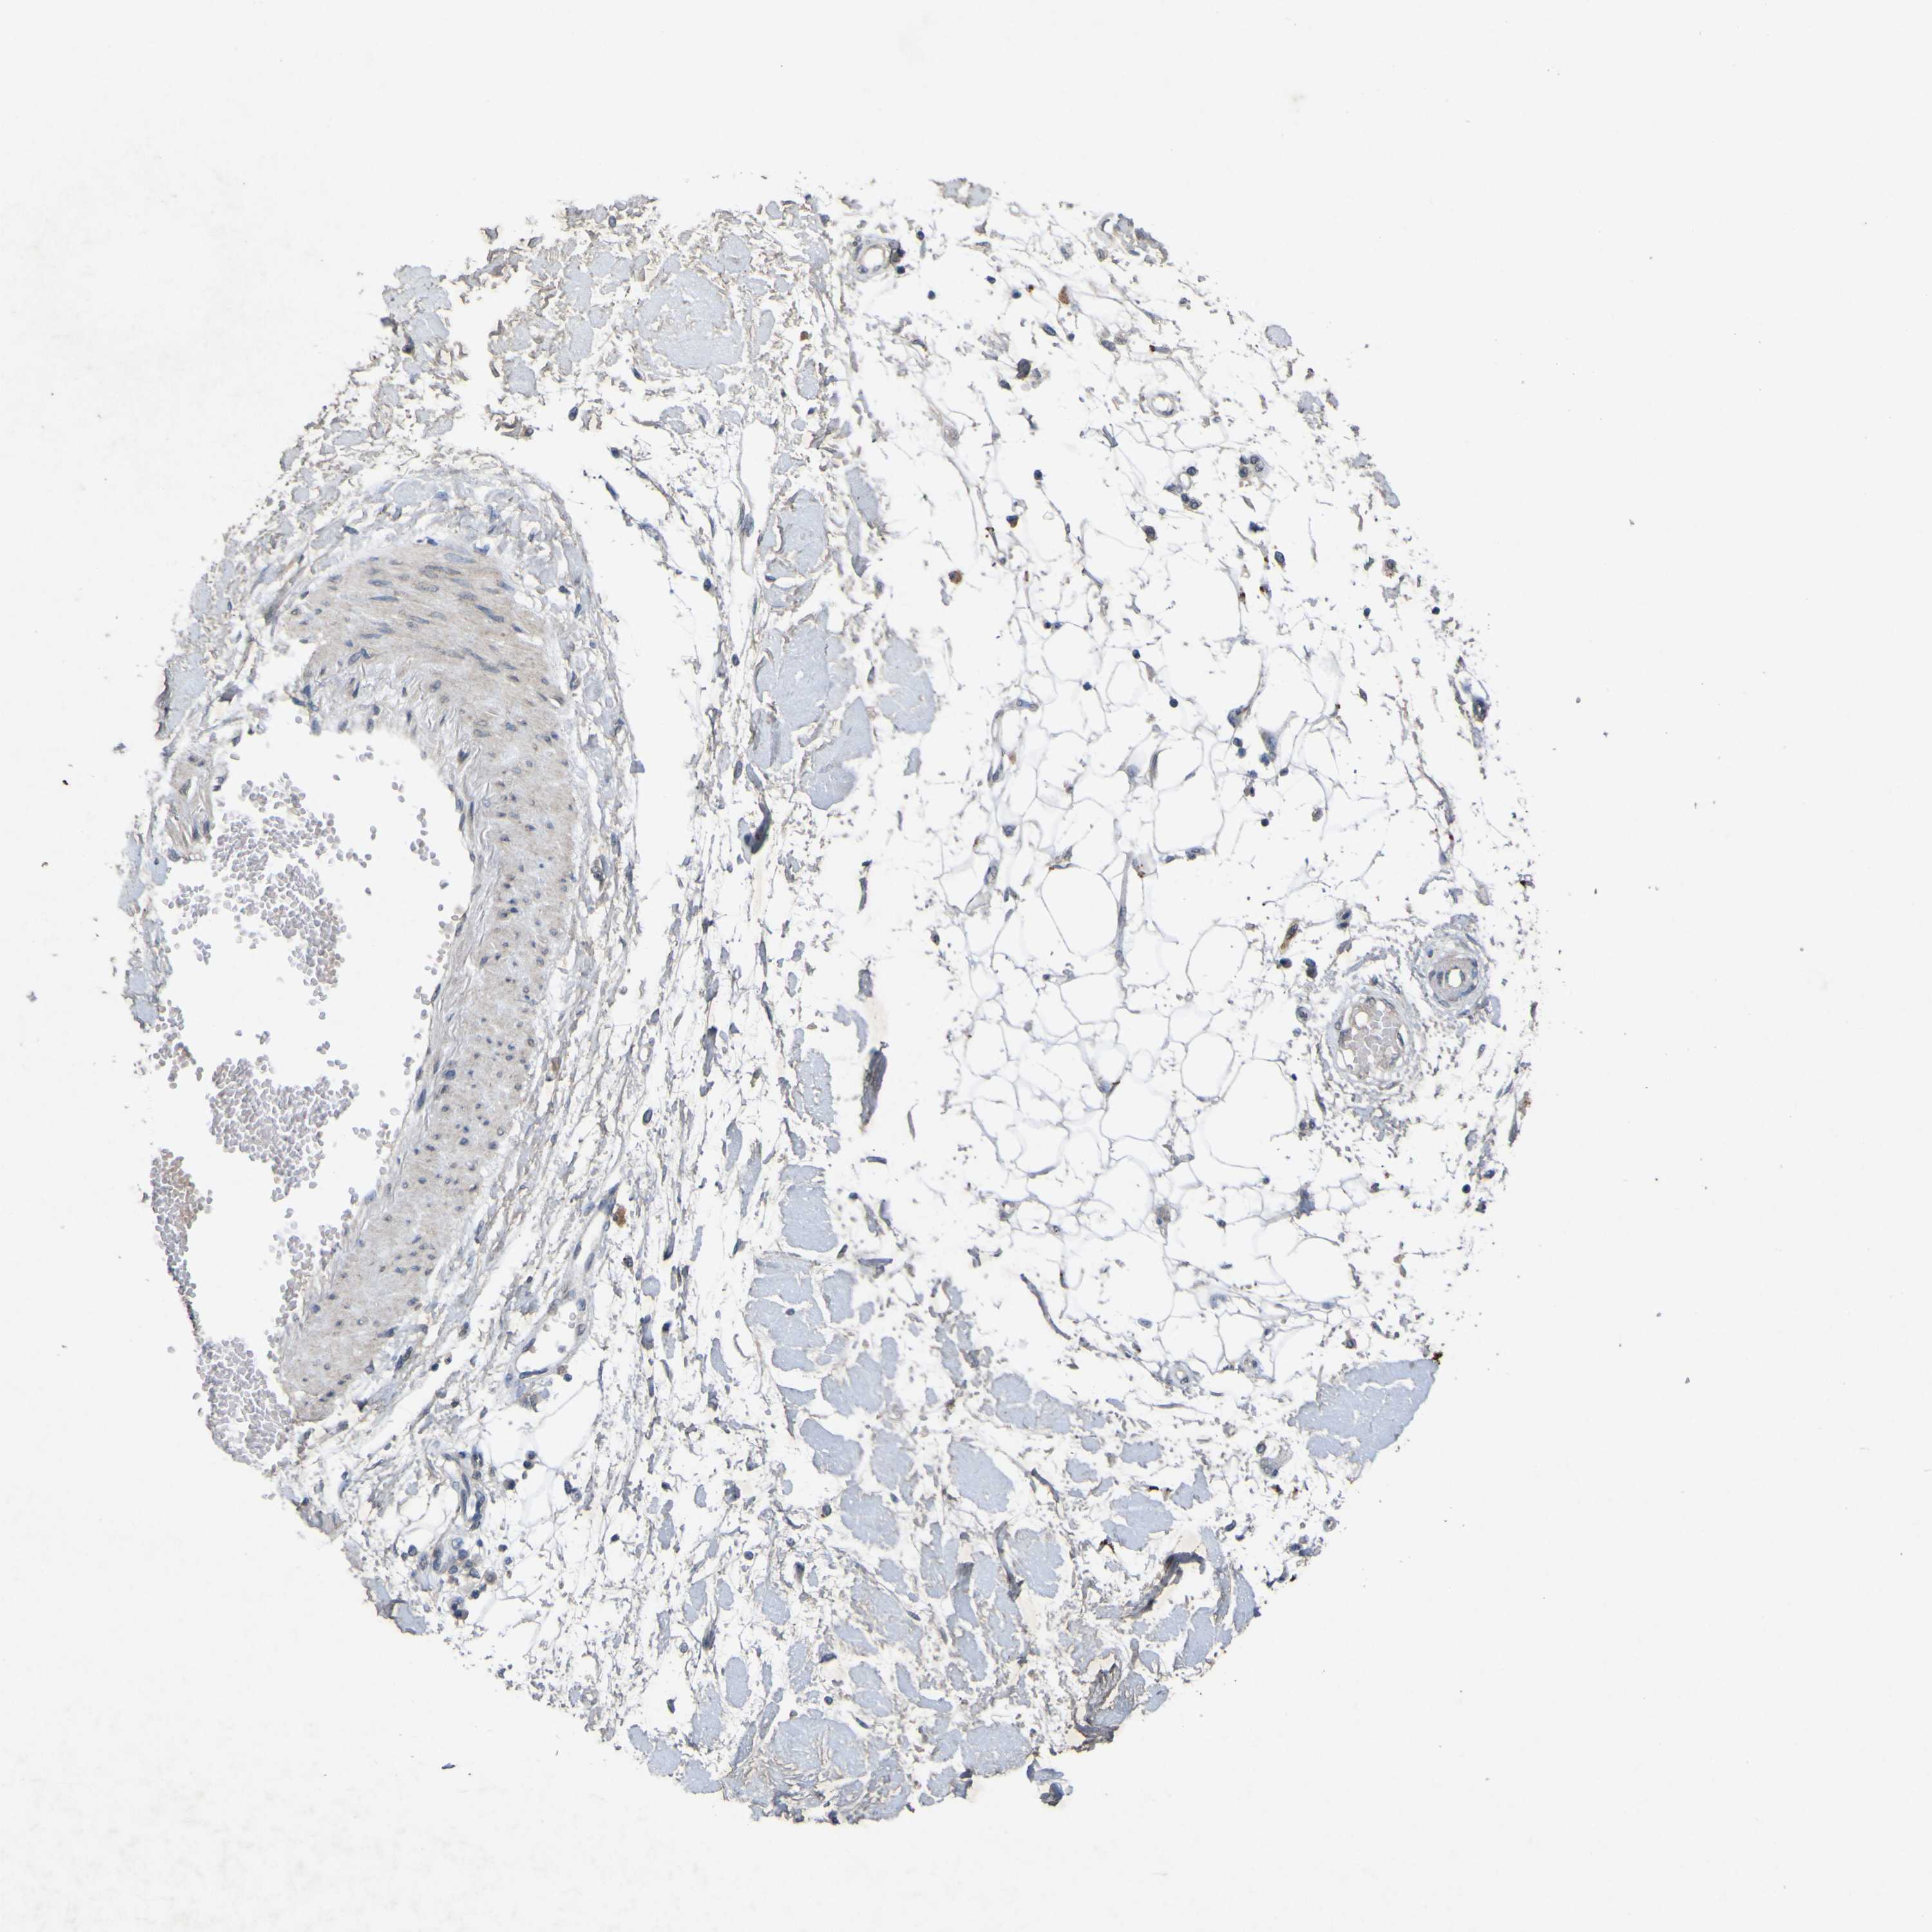

PRKCG